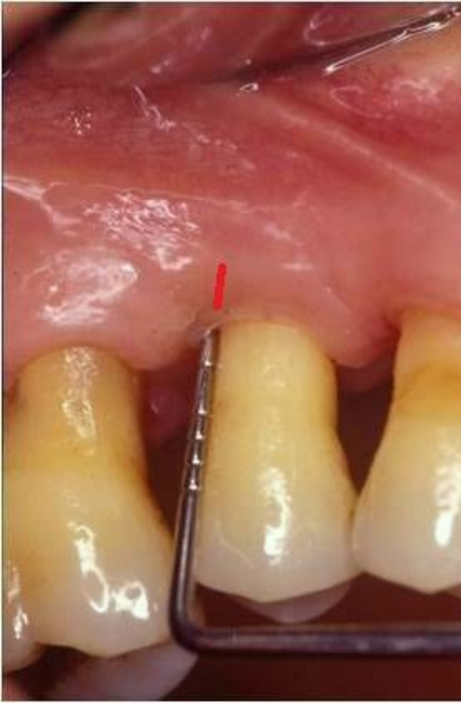

La microchirurgia plastica parodontale è utilizzata per arrestare la progressione di malattie parodontali e delle recessioni gengivali (retrazione delle gengive), ma anche per migliorare l’aspetto estetico della linea gengivale e del sorriso.

Radici dentali esposte sono il risultato della recessione gengivale. I denti in questi casi spesso sono sensibili a cibi e liquidi caldi, freddi o acidi. Le cause per cui si hanno recessioni gengivali sono le stessa da cui originano le parodontiti, prime tra tutte placca batterica, scarsa igiene orale, traumatismi, fumo. Esistono poi una varietà di fattori predisponenti che dovrebbero essere individuati per limitarne l’azione distruttiva e per prevenire l’ulteriore perdita di gengiva ed osso.

Innesti di tessuto molle possono essere utilizzati per coprire le radici esposte ma anche per ricostruire il tessuto che è andato perso. Il tessuto molle viene prelevato dal palato o da altre zone intraorali. L’intervento è quasi indolore e non esistono possibilità di rigetti. Il tessuto prelevato dalla zona donatrice si riforma spontaneamente in poche settimane.

Numerosi benefici derivano dalla chirurgia plastica parodontale: l’innesto di tessuto molle ricostruisce il tessuto perso e previene l’ulteriore progressione della recessione gengivale e dell’osso alveolare. Gli innesti gengivali riducono la sensibilità del dente e prevengono la formazione delle carie alle radici. E soprattutto migliorano l’aspetto estetico della linea gengivale e quindi del sorriso di ogni paziente.